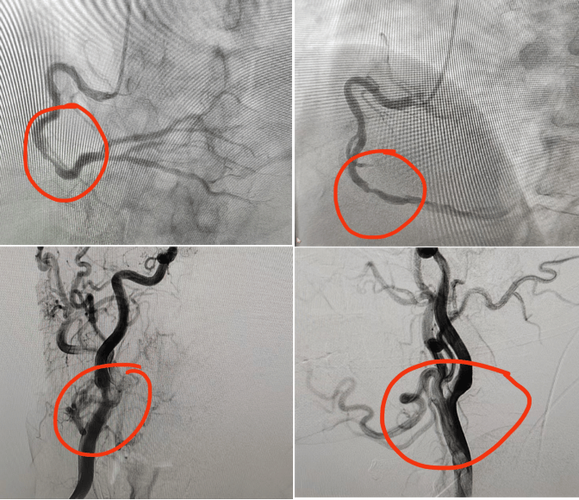

- 导管导航: 在X光机(DSA,数字减影血管造影机)的实时监控下,医生像“开赛车”一样,将导管从大腿或手腕的动脉,沿着主动脉、颈动脉,一路精确地导航到脑部的血管。

- 造影和成像: 当导管到达目标血管位置后,会注入一种造影剂,这种造影剂在X光下不透光,能让血管清晰地显影,这样,医生就能实时观察到脑部血管是否有狭窄、堵塞、畸形、动脉瘤等情况。

- 治疗(如果需要): 如果在检查中发现问题,可以立即进行治疗,这被称为“介入治疗”。

- 机械取栓: 对于急性大血管闭塞,可以通过导管送入取栓支架,直接将血栓拉出,恢复血流。

- 球囊扩张/支架植入: 对于血管严重狭窄,可以用球囊撑开狭窄部位,或植入支架,保持血管通畅。

脑梗血管造影是一项微创手术,但它也是目前诊断脑血管狭窄、闭塞等疾病的“金标准”,并且在诊断的同时具备强大的治疗能力(尤其是急性脑梗的取栓治疗)。

它是在影像设备引导下,通过穿刺血管、送入导管来完成的,存在一定的手术风险,因此需要由经验丰富的神经介入医生在专门的导管室内操作,对于疑似大血管闭塞的急性脑梗患者,这往往是挽救生命和功能的关键一步。